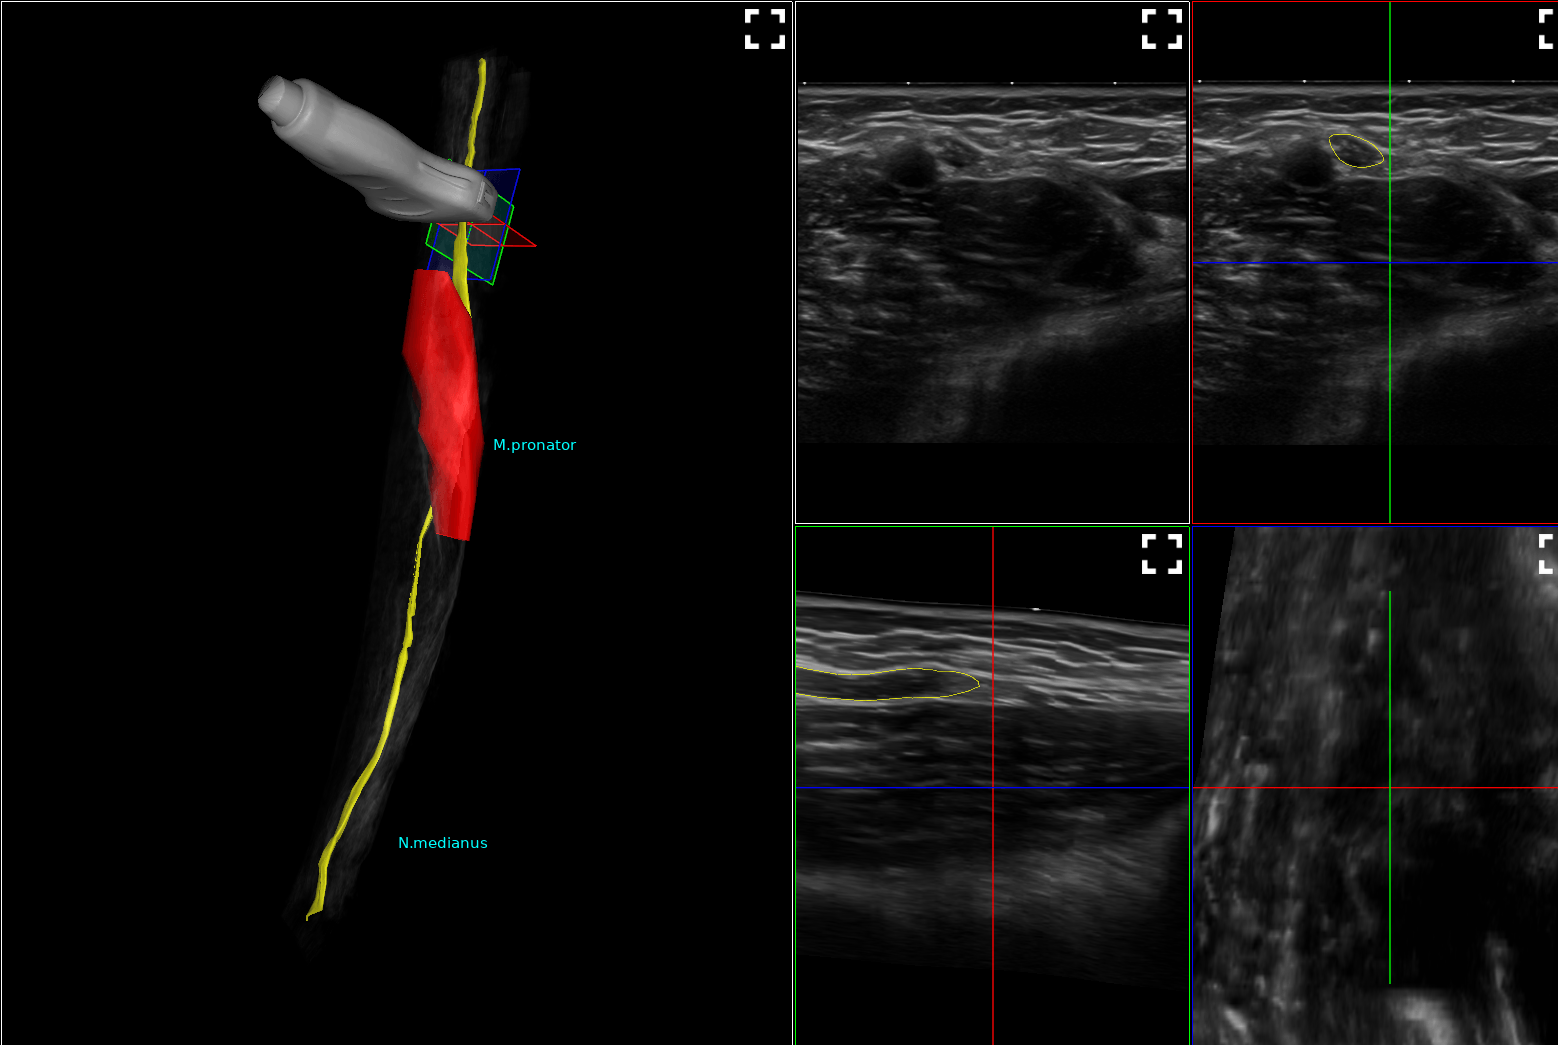

Heute wurde in unserer Praxis das weltweit erste mobile System zur 3-dimensionalen Darstellung von Nervenbahnen installiert. Hiermit können wir Veränderungen an Nerven noch präziser und v.a. anschaulich darstellen. Zudem können die Bilddaten exportiert und Ihnen mitgegeben werden (in Kooperation mit dem Hersteller in Vorbereitung), damit auch Kollegen wie z.B. Chirurgen sich ein noch besseres Bild machen können.